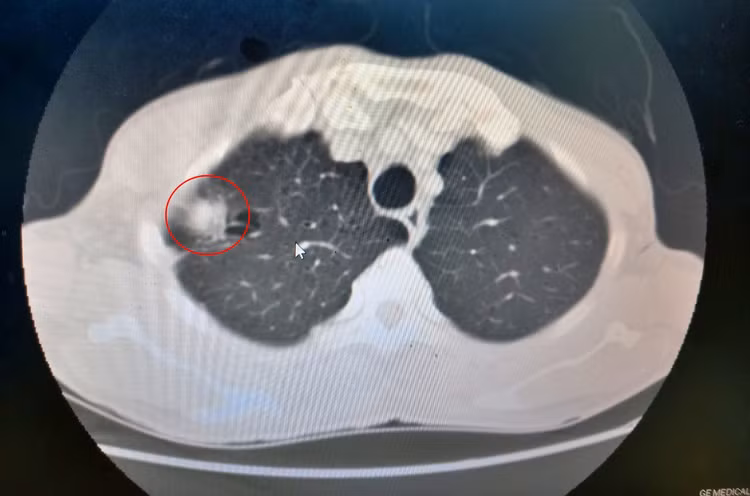

Bệnh nhân là P.N.H (65 tuổi) ở phường Hồng Hải, TP Hạ Long, gần đây ở nhà xuất hiện đau tức ngực, thỉnh thoảng ho nên đi khám, có tiền sử hút thuốc lá lâu năm. Qua thăm khám, chụp cắt lớp vi tính, bác sĩ phát hiện khối u thùy trên phổi phải.

Kết quả sinh thiết xác định đây là khối u ác tính, các bác sĩ chẩn đoán bệnh nhân bị ung thư phổi phải và quyết định thực hiện cắt khối u bằng phương pháp nội soi một đường rạch kèm vét hạch nhằm mang lại kết quả điều trị tốt nhất cho người bệnh.

Khối u ác tính phổi phải của bệnh nhân H. trên phim chụp cắt lớp vi tínhKhối u ác tính phổi phải của bệnh nhân H. trên phim chụp cắt lớp vi tính